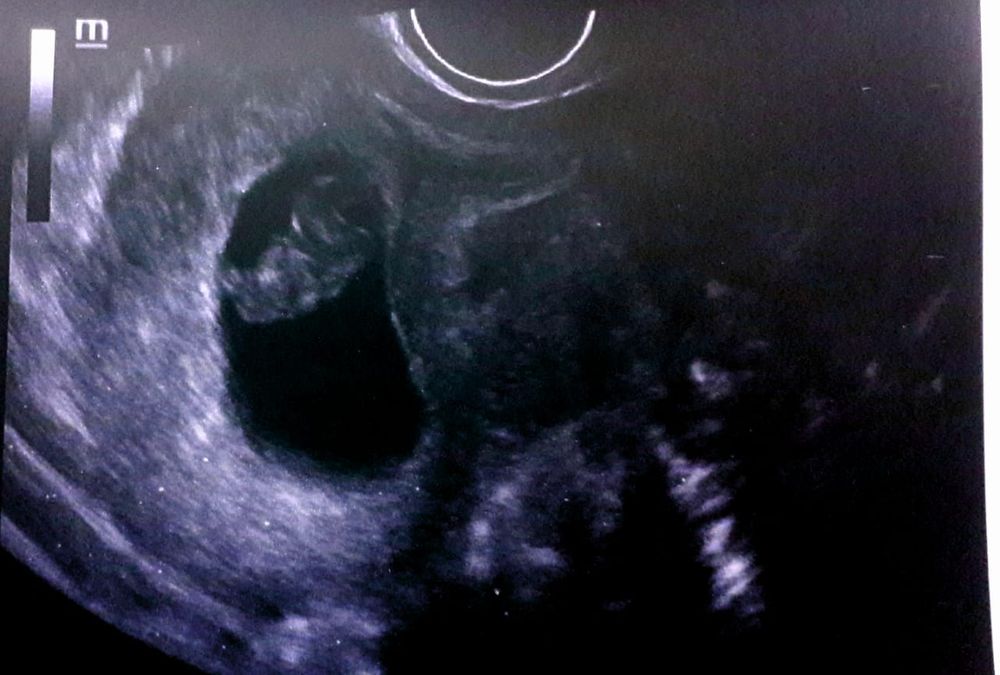

И вот поход в клинику для сдачи хгч и б подтверждают по узи. Затем поход на 2 узи и вот плод моей любви на сроке 8+5по мес.: